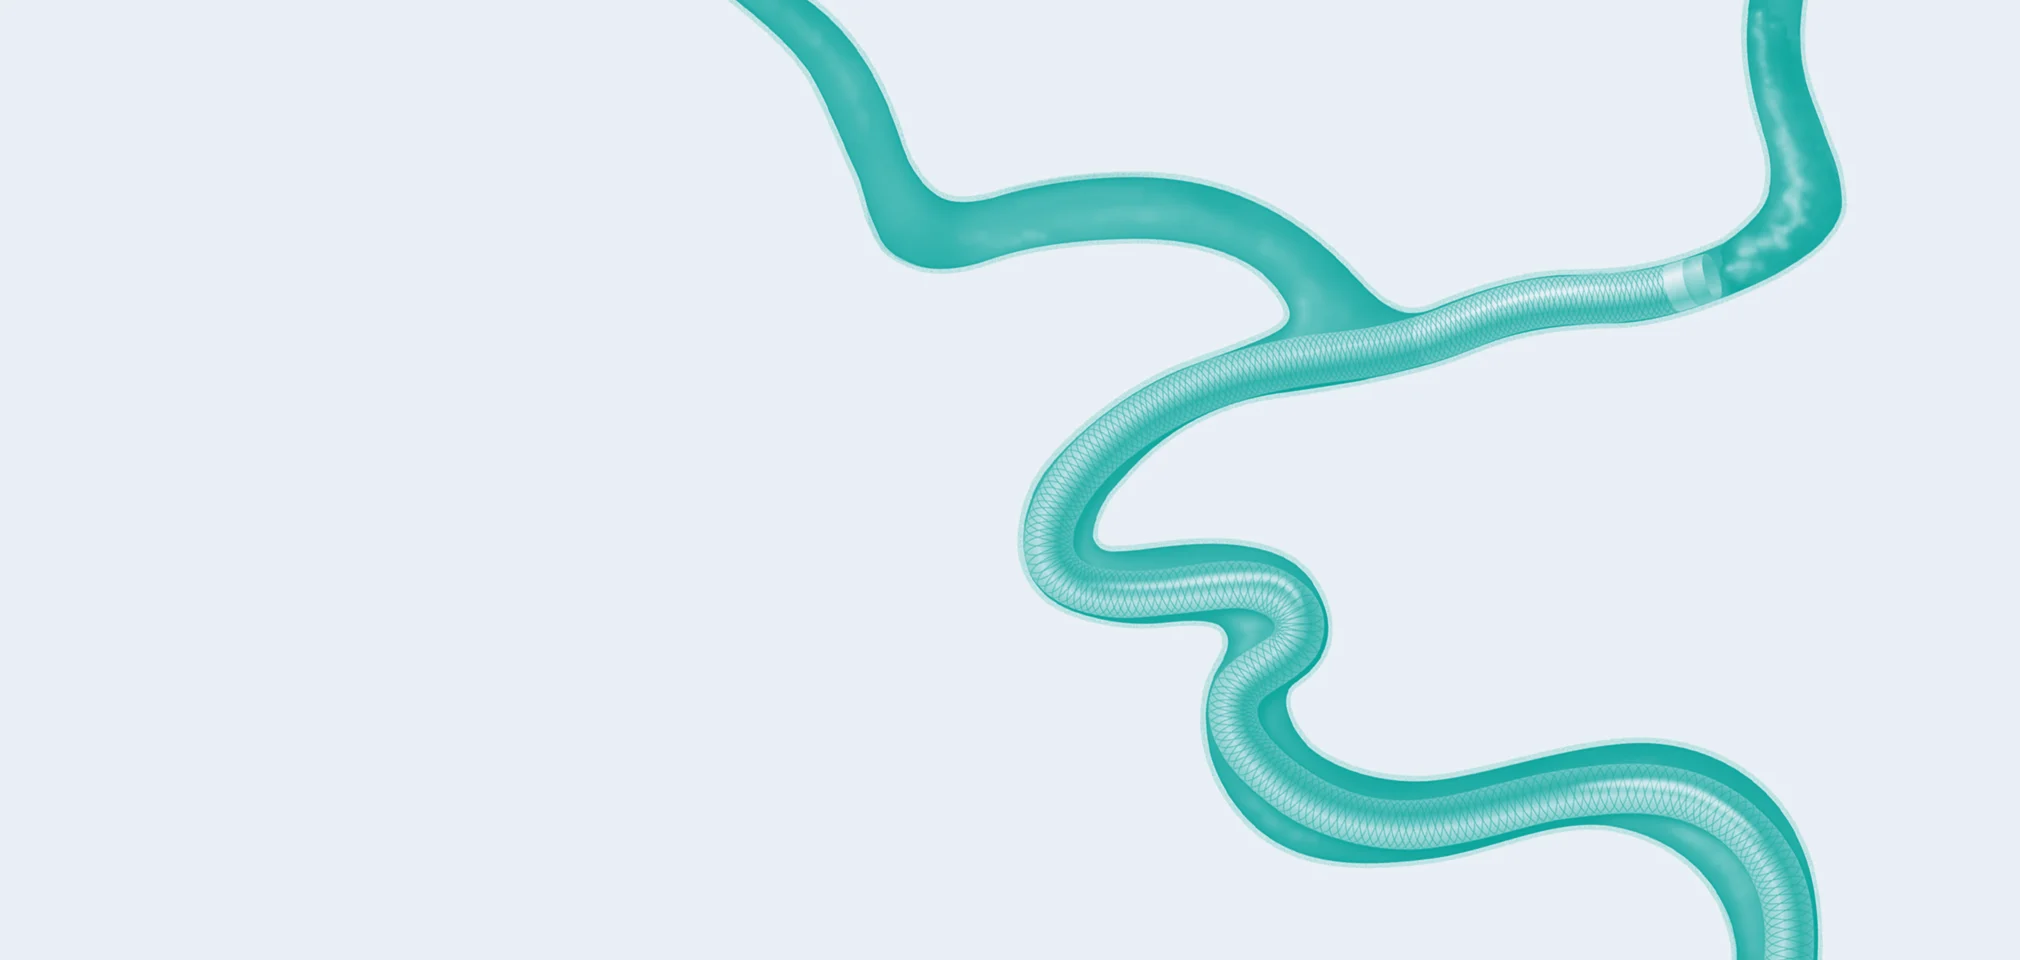

SOFIA™ Flow Plus

Aspiration Catheter